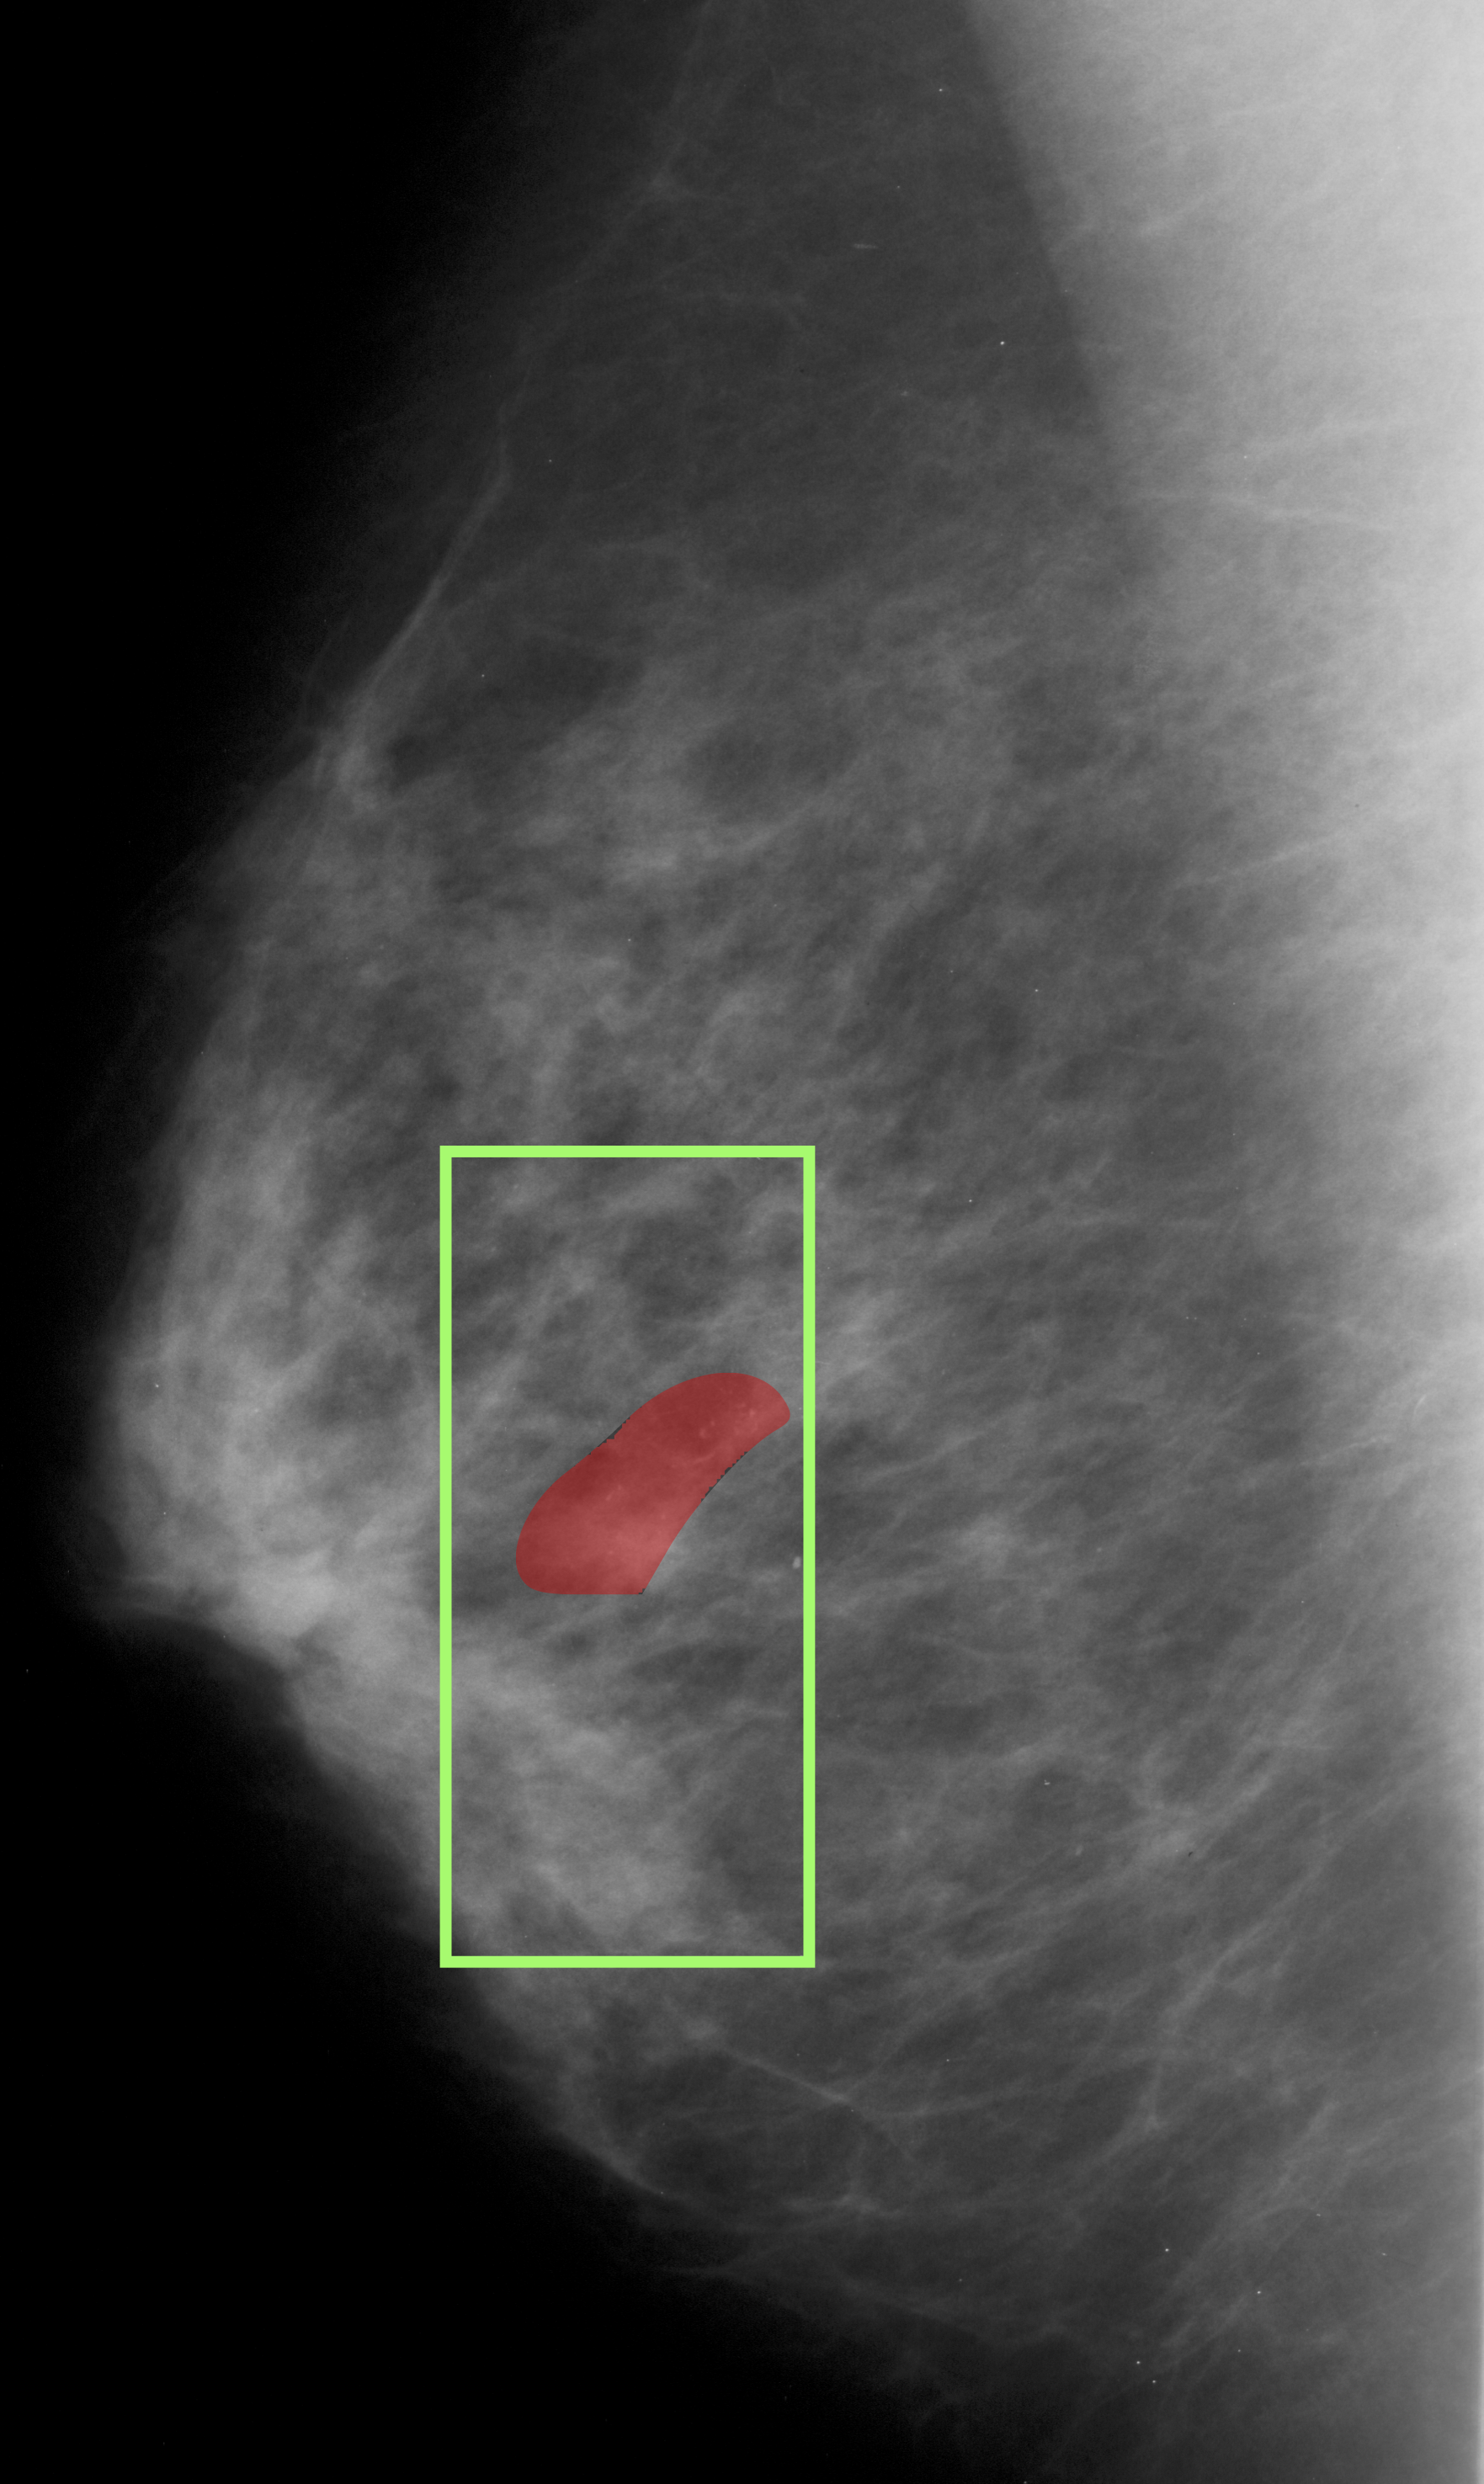

The proposed approach was also applied to breast cancer detection (for screening) from mammograms. Unlike the DME problem, evidence for breast cancer is not easily discernible to the naked, untrained eye and hence is particularly challenging. The 2 classes of interest were defined to be normal and abnormal. The latter includes benign and malignant cases as discrimination between these cases is difficult and best done by a specialised model. The ROI prediction aimed at are suspect regions regardless of whether they are benign or malignant. The architecture used for the DME problem was used and patches from the entire mammogram was fed as input. Training methodology was as described in section 2.3. The patches(200x200) which were classified as positive by the model acts as the predicted ROI in the large sized mammogram image(around 4000x4000 in dimension). The model was assessed on CBIS-DDSM dataset [14]. A total of 5218 training images (2017 abnormal and 3201 Normal) were split into train and validation in the ratio of 12:5. A model trained on 1:3 ratio of annotated images, was evaluated on a test set of 1298 images(709 abnormal and 589 Normal). The AUC/sensitivity(SN)%/specificity(SP)% attained was 0.98/90/93 respectively. Three sample images with ground truth regions and model-predicted ROIs(bounding boxes) are shown in Fig.5. A baseline model(Mbsubscript𝑀𝑏M_{b}) was also trained and tested. It achieved a AUC/SN/SP of 0.972/88.2/ 91.3 respectively. A recent method [15] that does normal/cancerous classification also reports on [14]. It is based on transfer learning with a Resnet50 and reports AUC/SN/SP to be 0.91/86%/80.1%.

Figure 5: Breast cancer detection. Green - Predicted ROI, Red - Ground Truth.